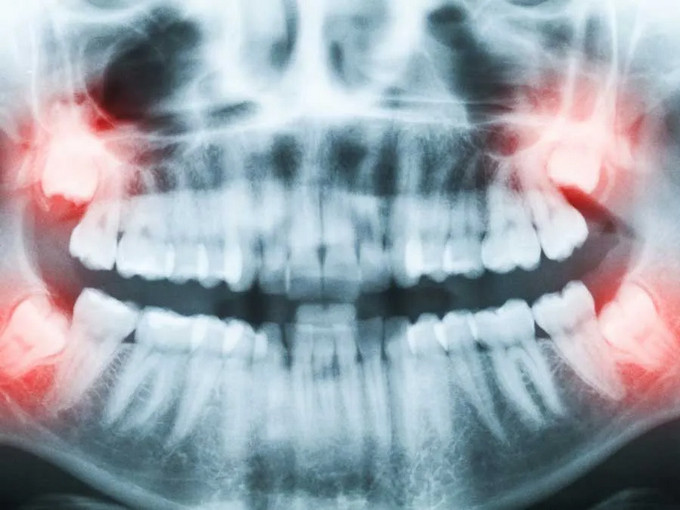

智齒通常在18~25歲萌出。因?yàn)轭M骨空間不足、牙胚位置異常或角度不正,智齒長(zhǎng)不出來,斜著或橫著長(zhǎng),被牙齦或骨頭部分或完全覆蓋,就稱為埋伏(阻生)智齒。這類智齒與口腔之間常形成難以清潔的“盲袋”,為細(xì)菌聚集提供條件。

4. 形成囊腫或出現(xiàn)占位:影像可見病灶擴(kuò)大、骨質(zhì)被吸收。

智齒通常在18~25歲萌出。因?yàn)轭M骨空間不足、牙胚位置異?;蚪嵌炔徽?,智齒長(zhǎng)不出來,斜著或橫著長(zhǎng),被牙齦或骨頭部分或完全覆蓋,就稱為埋伏(阻生)智齒。這類智齒與口腔之間常形成難以清潔的“盲袋”,為細(xì)菌聚集提供條件。